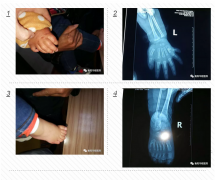

正常人一般只有兩個(gè)大拇指,可家住衡陽(yáng)縣集兵鎮(zhèn)的1歲大的城城,雙手和雙腳比常人各多出1個(gè)小手指和1個(gè)小腳趾,不過(guò)在衡陽(yáng)華程醫(yī)院骨科中心醫(yī)護(hù)人員的幫助下,3月23日下午,多出來(lái)的手指和腳趾已被成功切除。 面對(duì)這位只有1歲的小患者,骨科中心醫(yī)護(hù)人員進(jìn)行